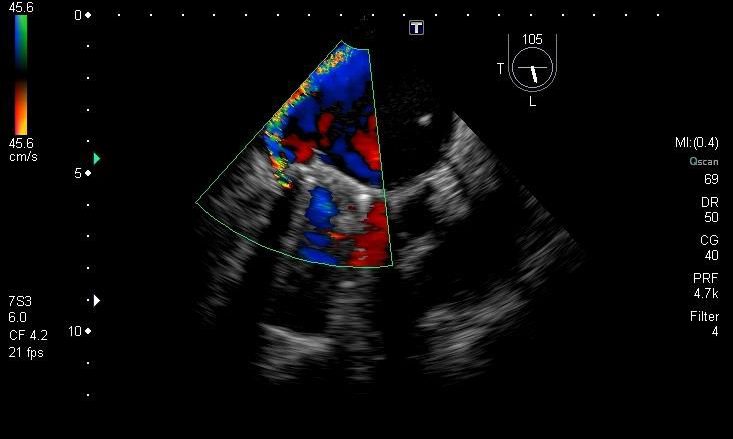

Cierre Endovascular de Leak Paravalvular

Se trata de una complicación poco frecuente del implante de prótesis valvular. El Dr. Claudio Cigalini, Jefe del Servicio de Diagnóstico y Tratamiento Endovascular de Grupo Gamma, nos cuenta cómo se realizó la intervención quirúrgica. En la misma, trabajaron en forma conjunta el Departamento de Cardiología, el Servicio de Diagnóstico y Tratamiento Endovascular, y el Servicio de Cirugía Torácica y Cardiovascular y Servicio de […]